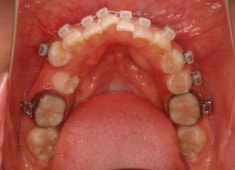

治療開始時